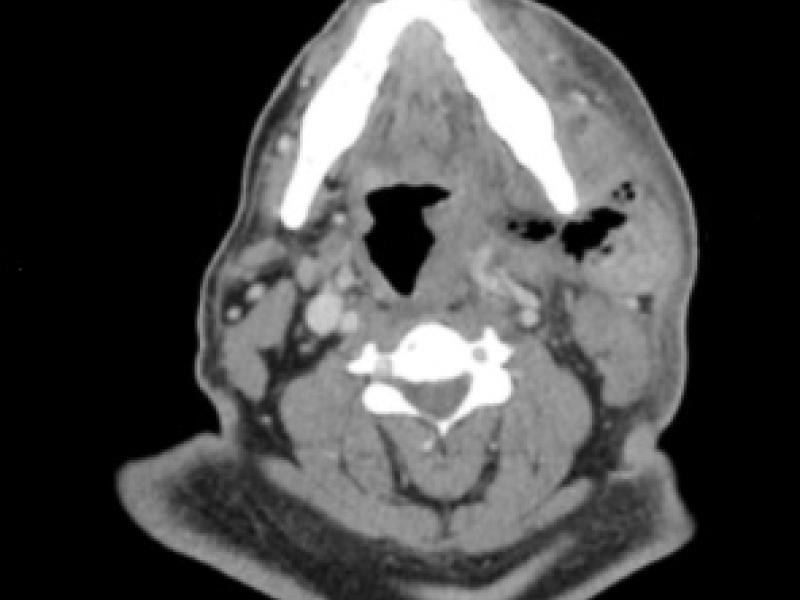

A 50 yo M presents to the ED w/ dental pain and facial